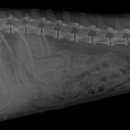

• 24시 에피소드 동물 메디컬 센터 | 만촌동 동물병원 강아지 요골·척골 골절 수술 후기 [24시에피소드동물메디컬센터]

만촌동 동물병원 강아지 요골·척골 골절 수술 후기 [24시에피소드동물메디컬센터] 만촌동 동물병원 ​ 안녕하세요. ​ 풍부한 경험과 따듯한 진료를 바탕으로, 반려동물의 건강하고 행복한 하루하루를 함께 만들어 가는 만촌동 동물병원 24시에피소드동물메디컬센터 입니다. 24시에피소드동물메디컬센터 대구광역시 동구...

에피소드동물메디컬센터(2025-06-26 12:41:00)